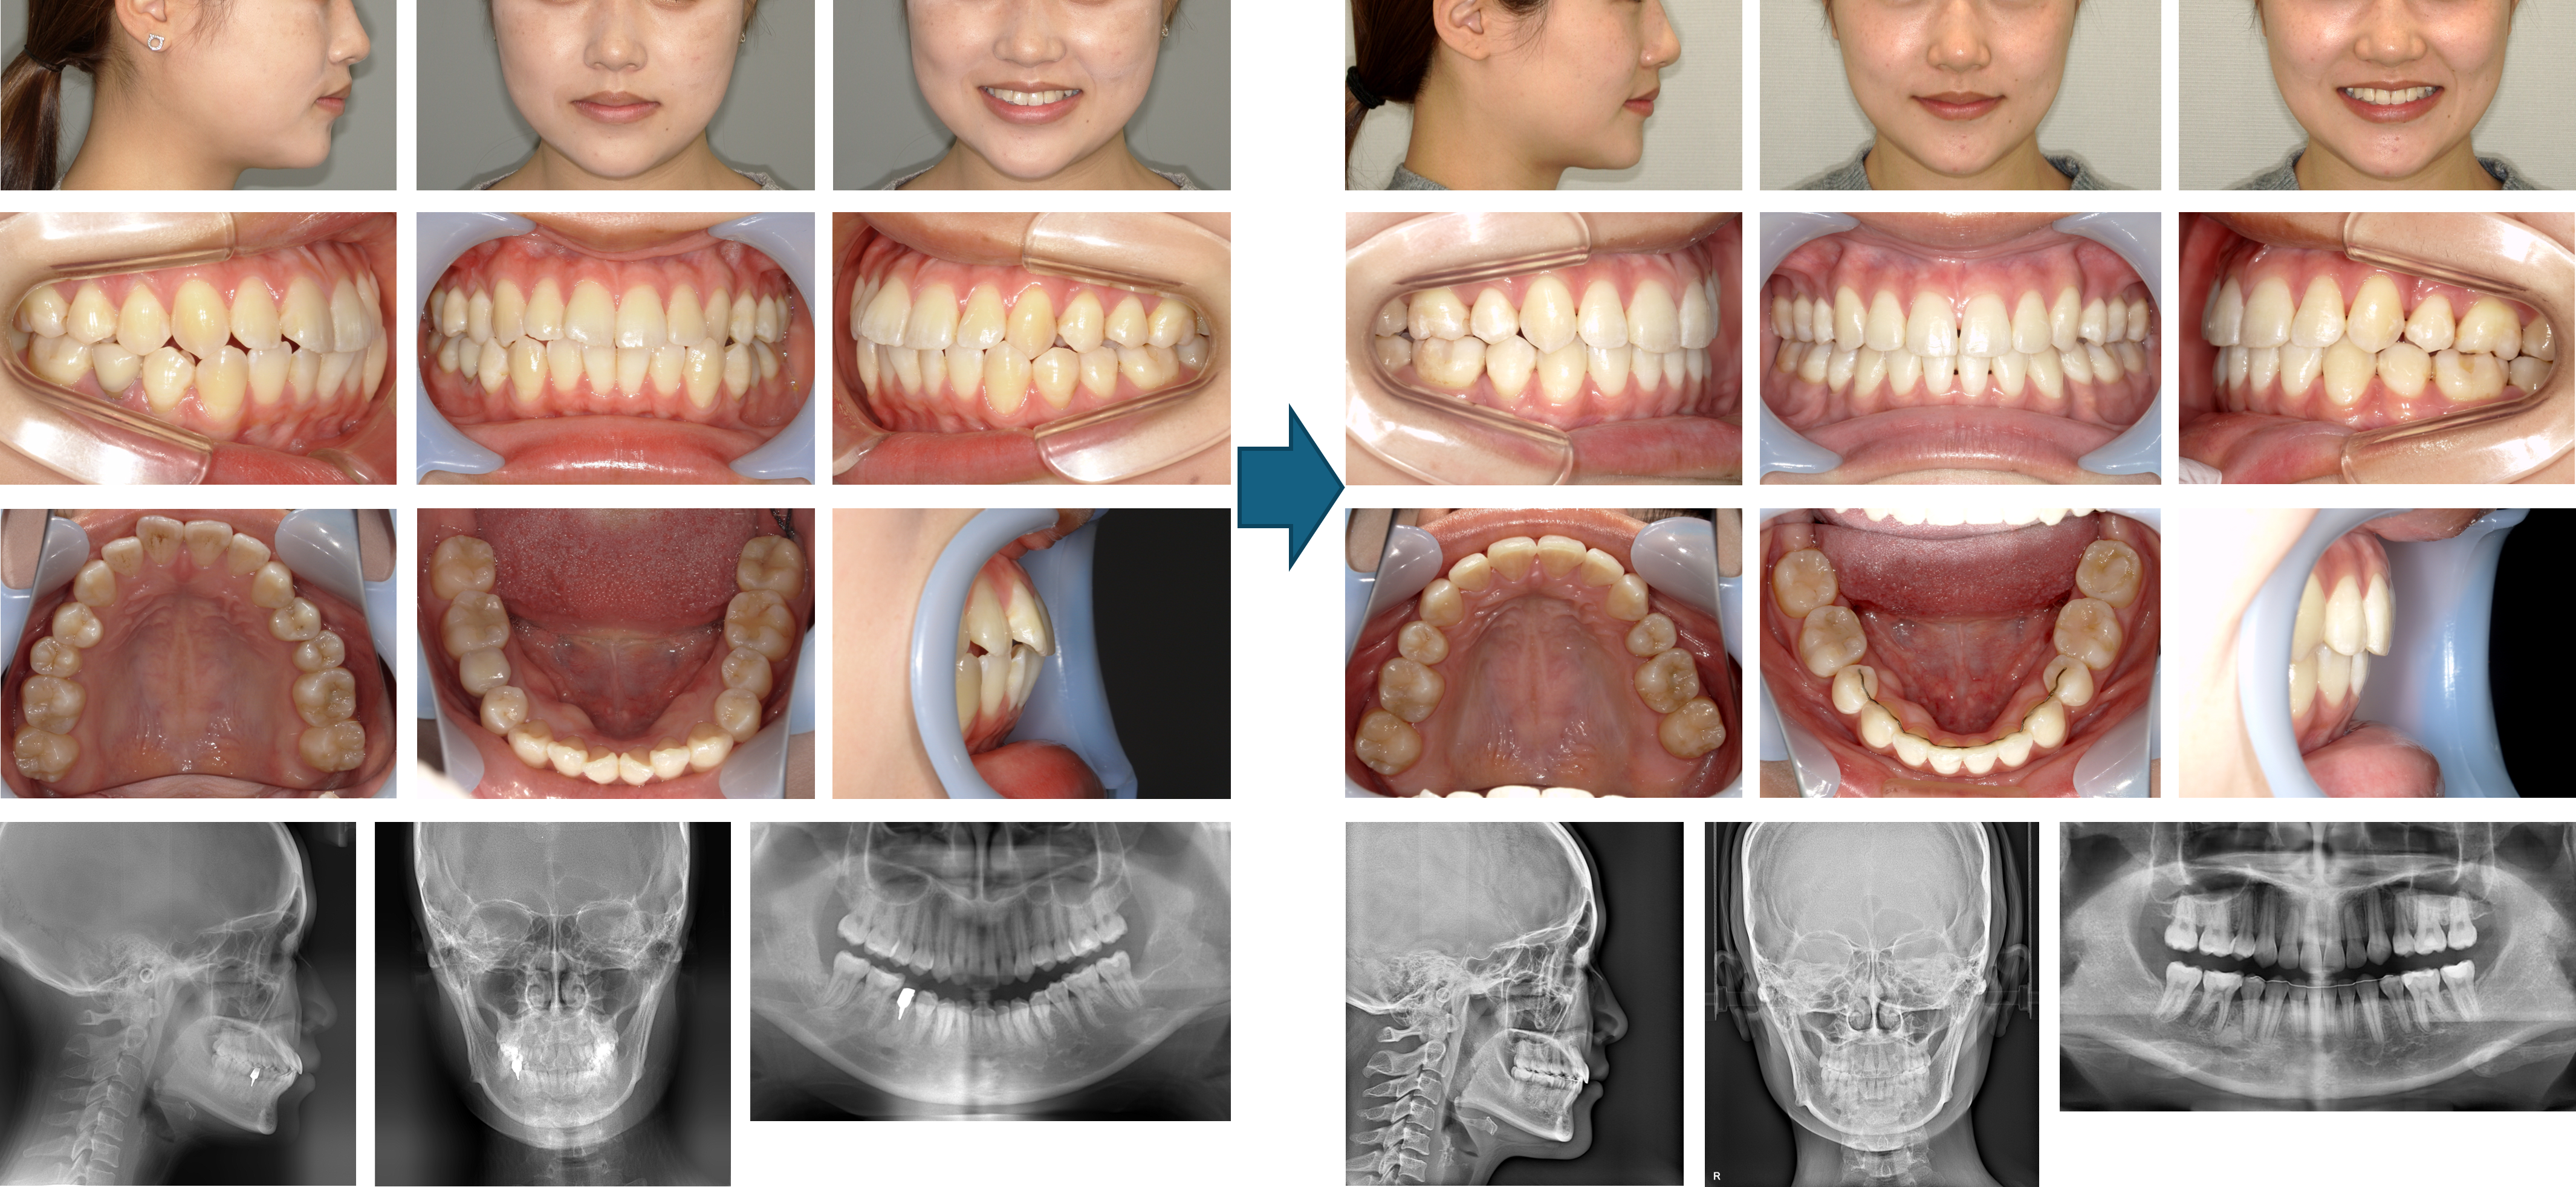

【治療例】初診時年齢:15歳2か月 / 性別:男性 / 主訴:上の前歯が出ている

症例の概要:上顎前歯の唇側傾斜によって口唇閉鎖時は上唇の突出とオトガイの過緊張が認められました。最初に上顎の抜歯を行い、下顎の抜歯は治療経過から考慮することを患者さんにお伝えして治療を開始しました。結果、下顎は一部の歯の隣接面を削ったが抜歯をせずに顔貌の改善および緊密な咬合を獲得することができました。

主訴:上の前歯が出ている

診断名: 著しく上顎前歯が唇側傾斜した下顎後退型の骨格性Ⅱ級、ローアングル症例

使用した主な装置: マルチブラケット装置(金属)、サービカルヘッドギア、顎間ゴム

抜歯/非抜歯および抜歯部位: 右上4番8番、左上4番、右下8番の抜歯

治療期間:2年9か月

治療回数:38回

リスクの副作用:歯の移動、装置による口内炎、抜歯などの痛みや歯肉退縮、歯根吸収、後戻りなどの可能性がある